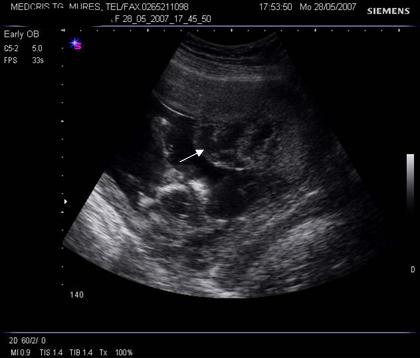

Fig. nr. 208. Placenta gr O la 16 saptamani gestationale, cu sageata se remarca insertia centrala placentara , a cordonului ombilical

Fig. nr.209 Placenta gr. I la o sarcina de 23 saptamani gestationale ( sageata indica ondulatiile minime ale placii choriale )